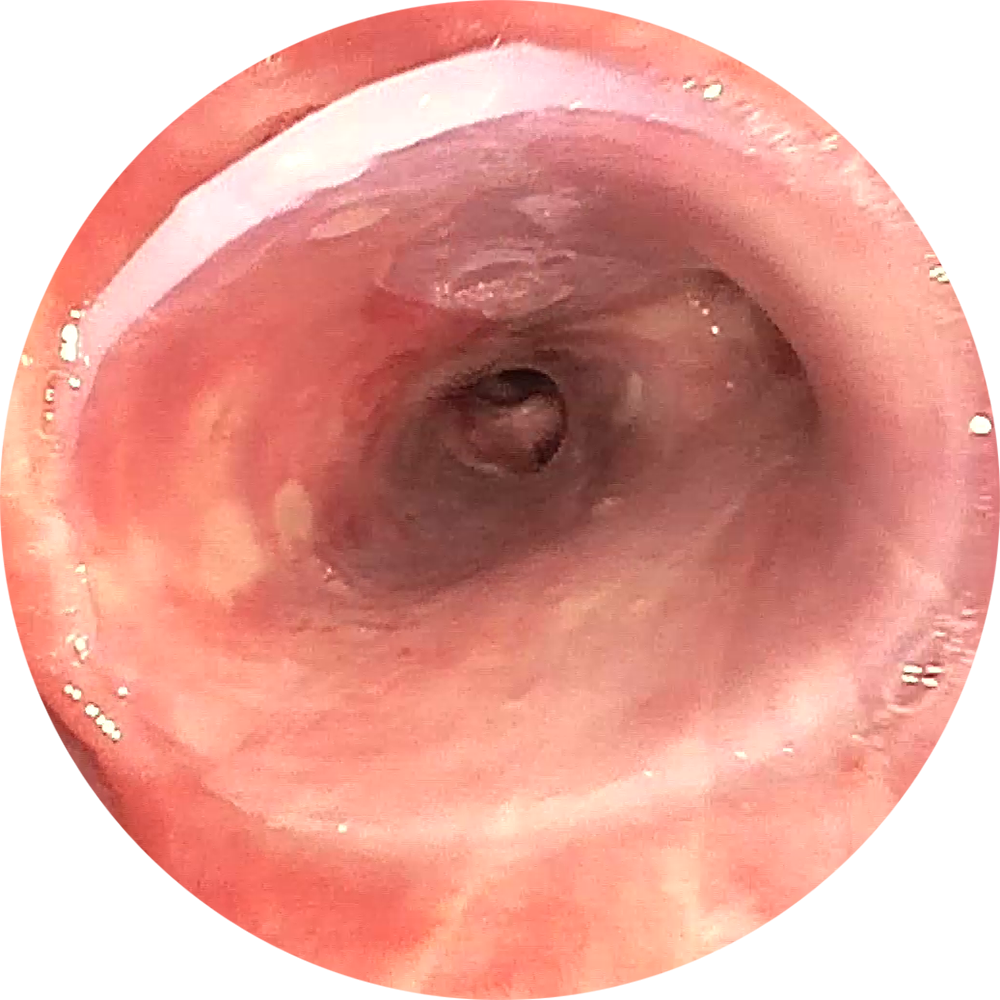

Erfolgreiche Implantation eines NOVATECH® 3D Stent bei einem Patienten mit Bronchomalazie im rechten Bronchus.

Bilder freundlicherweise zur Verfügung gestellt

von PD Dr. Daniel Franzen, Zürich.